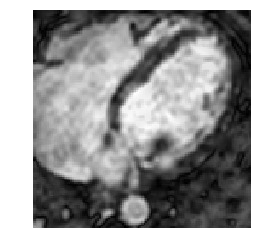

Medical image segmentation methods normally perform poorly when there is a domain shift between training and testing data. Unsupervised Domain Adaptation (UDA) addresses the domain shift problem by training the model using both labeled data from the source domain and unlabeled data from the target domain. Source-Free UDA (SFUDA) was recently proposed for UDA without requiring the source data during the adaptation, due to data privacy or data transmission issues, which normally adapts the pre-trained deep model in the testing stage. However, in real clinical scenarios of medical image segmentation, the trained model is normally frozen in the testing stage. In this paper, we propose Fourier Visual Prompting (FVP) for SFUDA of medical image segmentation. Inspired by prompting learning in natural language processing, FVP steers the frozen pre-trained model to perform well in the target domain by adding a visual prompt to the input target data. In FVP, the visual prompt is parameterized using only a small amount of low-frequency learnable parameters in the input frequency space, and is learned by minimizing the segmentation loss between the predicted segmentation of the prompted target image and reliable pseudo segmentation label of the target image under the frozen model. To our knowledge, FVP is the first work to apply visual prompts to SFUDA for medical image segmentation. The proposed FVP is validated using three public datasets, and experiments demonstrate that FVP yields better segmentation results, compared with various existing methods.